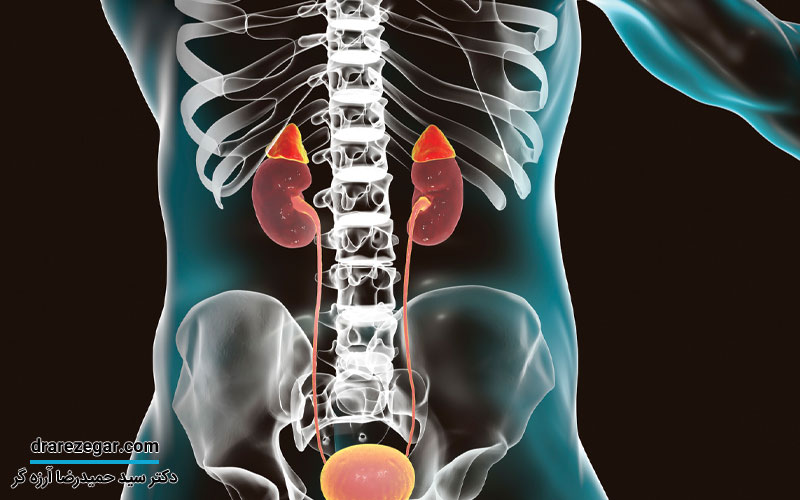

در اصطلاح پزشکی به غدد فوق کلیوی، غدد آدرنال گفته می شود که به صورت دو غده درون ریز بوده و هر کدام روی کلیه قرار می گیرد. وزن تقریبی هر کدام از این غده ها ۵ گرم است و به ۲ بخش قشر و مغز یا مدولا تقسیم می شوند. لازم به ذکر است که هر کدام از این دو بخش می توانند یکسری هورمون های متفاوت ترشح کنند.